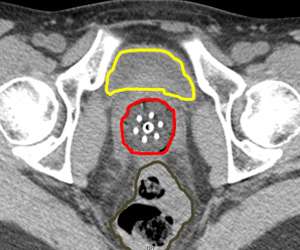

Below is an actual example of the CAPRI applicator (a 13 channel applicator) and the distribution of radiation dose that was delivered around the vaginal apex (right image axial and left image sagittal). Below to the right is a 3D depiction of the anatomy and distribution of the radiation dose (bladder in yellow, rectum in brown, applicator in purple, radiation dose in red):